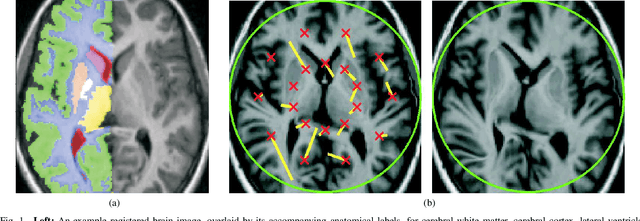

Abstract:We present a generic method for assessing the quality of non-rigid registration (NRR) algorithms, that does not depend on the existence of any ground truth, but depends solely on the data itself. The data is a set of images. The output of any NRR of such a set of images is a dense correspondence across the whole set. Given such a dense correspondence, it is possible to build various generative statistical models of appearance variation across the set. We show that evaluating the quality of the registration can be mapped to the problem of evaluating the quality of the resultant statistical model. The quality of the model entails a comparison between the model and the image data that was used to construct it. It should be noted that this approach does not depend on the specifics of the registration algorithm used (i.e., whether a groupwise or pairwise algorithm was used to register the set of images), or on the specifics of the modelling approach used. We derive an index of image model specificity that can be used to assess image model quality, and hence the quality of registration. This approach is validated by comparing our assessment of registration quality with that derived from ground truth anatomical labeling. We demonstrate that our approach is capable of assessing NRR reliably without ground truth. Finally, to demonstrate the practicality of our method, different NRR algorithms -- both pairwise and groupwise -- are compared in terms of their performance on 3D MR brain data.